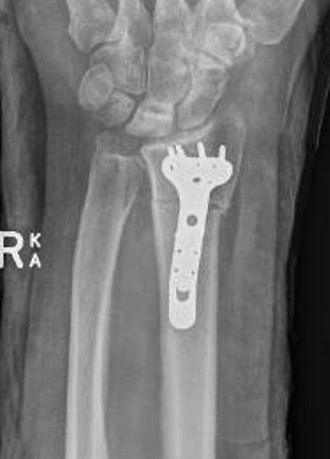

Stage II / IIIA

Radial Shortening +/- vascularized bone graft

Indication

Negative ulna variance

Technique

Trimed distal shortening osteotomy plate

Volar approach / bed of FCR

- osteotomy distal to DRUJ

- resection of desired amount

- aim for neutral or +1 mm ulnar variance

- usually 2 - 3 mm

- cutting guides available

- volar plate